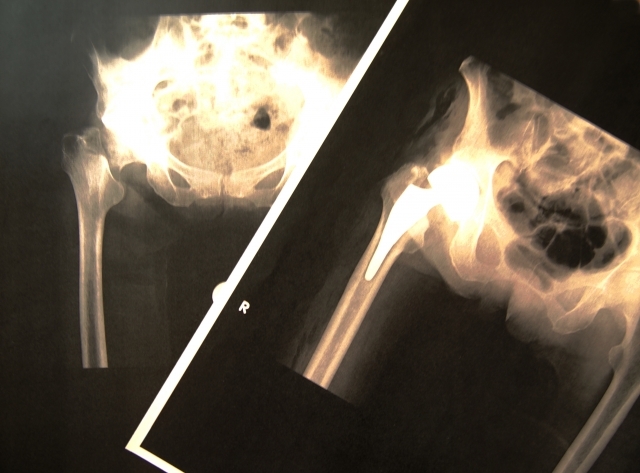

第3章:最初のサインは骨折のこともある

整形外科では、軽いきっかけでの骨折から病気が発覚するケースをよく診ます。以下のサインに心当たりはありませんか?

- 転んだだけで手首を骨折した

- くしゃみや体をひねっただけで背中に激痛が走る

- 以前より明らかに身長が低くなった

これらは単なる「不注意」や「加齢」ではなく、骨密度の低下が招いた結果かもしれません。「もっと早く分かっていれば」と後悔する前に、現状を知ることが大切です。

第4章:整形外科でできることと考え方

整形外科では骨密度検査を行い、客観的なデータに基づいて対策を検討します。一度検査して終わりではなく、継続的な管理が重要になります。